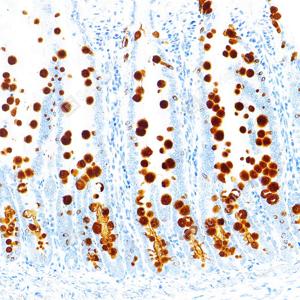

IHC检测MUC2蛋白(货号 GB15344). 样品: 人结肠癌, 4%多聚甲醛 (货号G1101) 固定12-24小时. 抗原修复: 柠檬酸抗原修复液(干粉, pH 6.0) (G1201), 高压锅均匀喷气计时2分钟. —抗: 1: 1000稀释, 4℃ 孵育过夜. 二抗: S-vision免疫组化多聚二抗(山羊抗兔),即用型 (货号G1302), 室温孵育20分钟. |